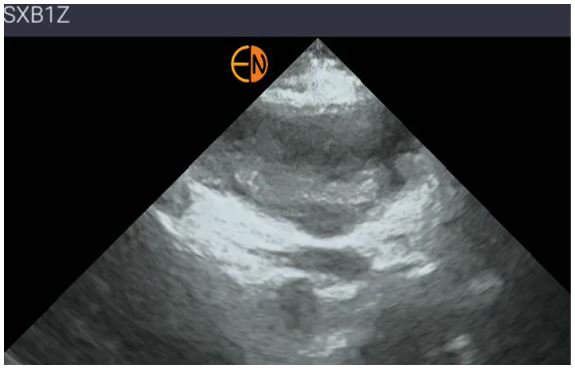

Realizamos ecografía clínica donde se evidencia engrosamiento de tejido celular subcutáneo con hipercaptación Doppler sin visualizar abscesos, además de contenido hiperecogénico intravesical. A nivel pulmonar patrón de líneas A sin consolidaciones.

La POCUS multiórgano fue decisiva: mostró la presencia de material hiperecogénico en vejiga como posible origen del cuadro, confirmó celulitis sin absceso y descartó otros focos infecciosos. Se acortaron tiempos diagnósticos, orientamos la derivación hospitalaria de forma precisa y facilitamos el inicio precoz de antibioterapia. No es solo un complemento, sino una herramienta transformadora: convierte la incertidumbre en seguridad, protege a los pacientes más vulnerables y optimiza recursos. Marca la diferencia entre sospechar y confirmar, entre demora y oportunidad, entre complicación y supervivencia.